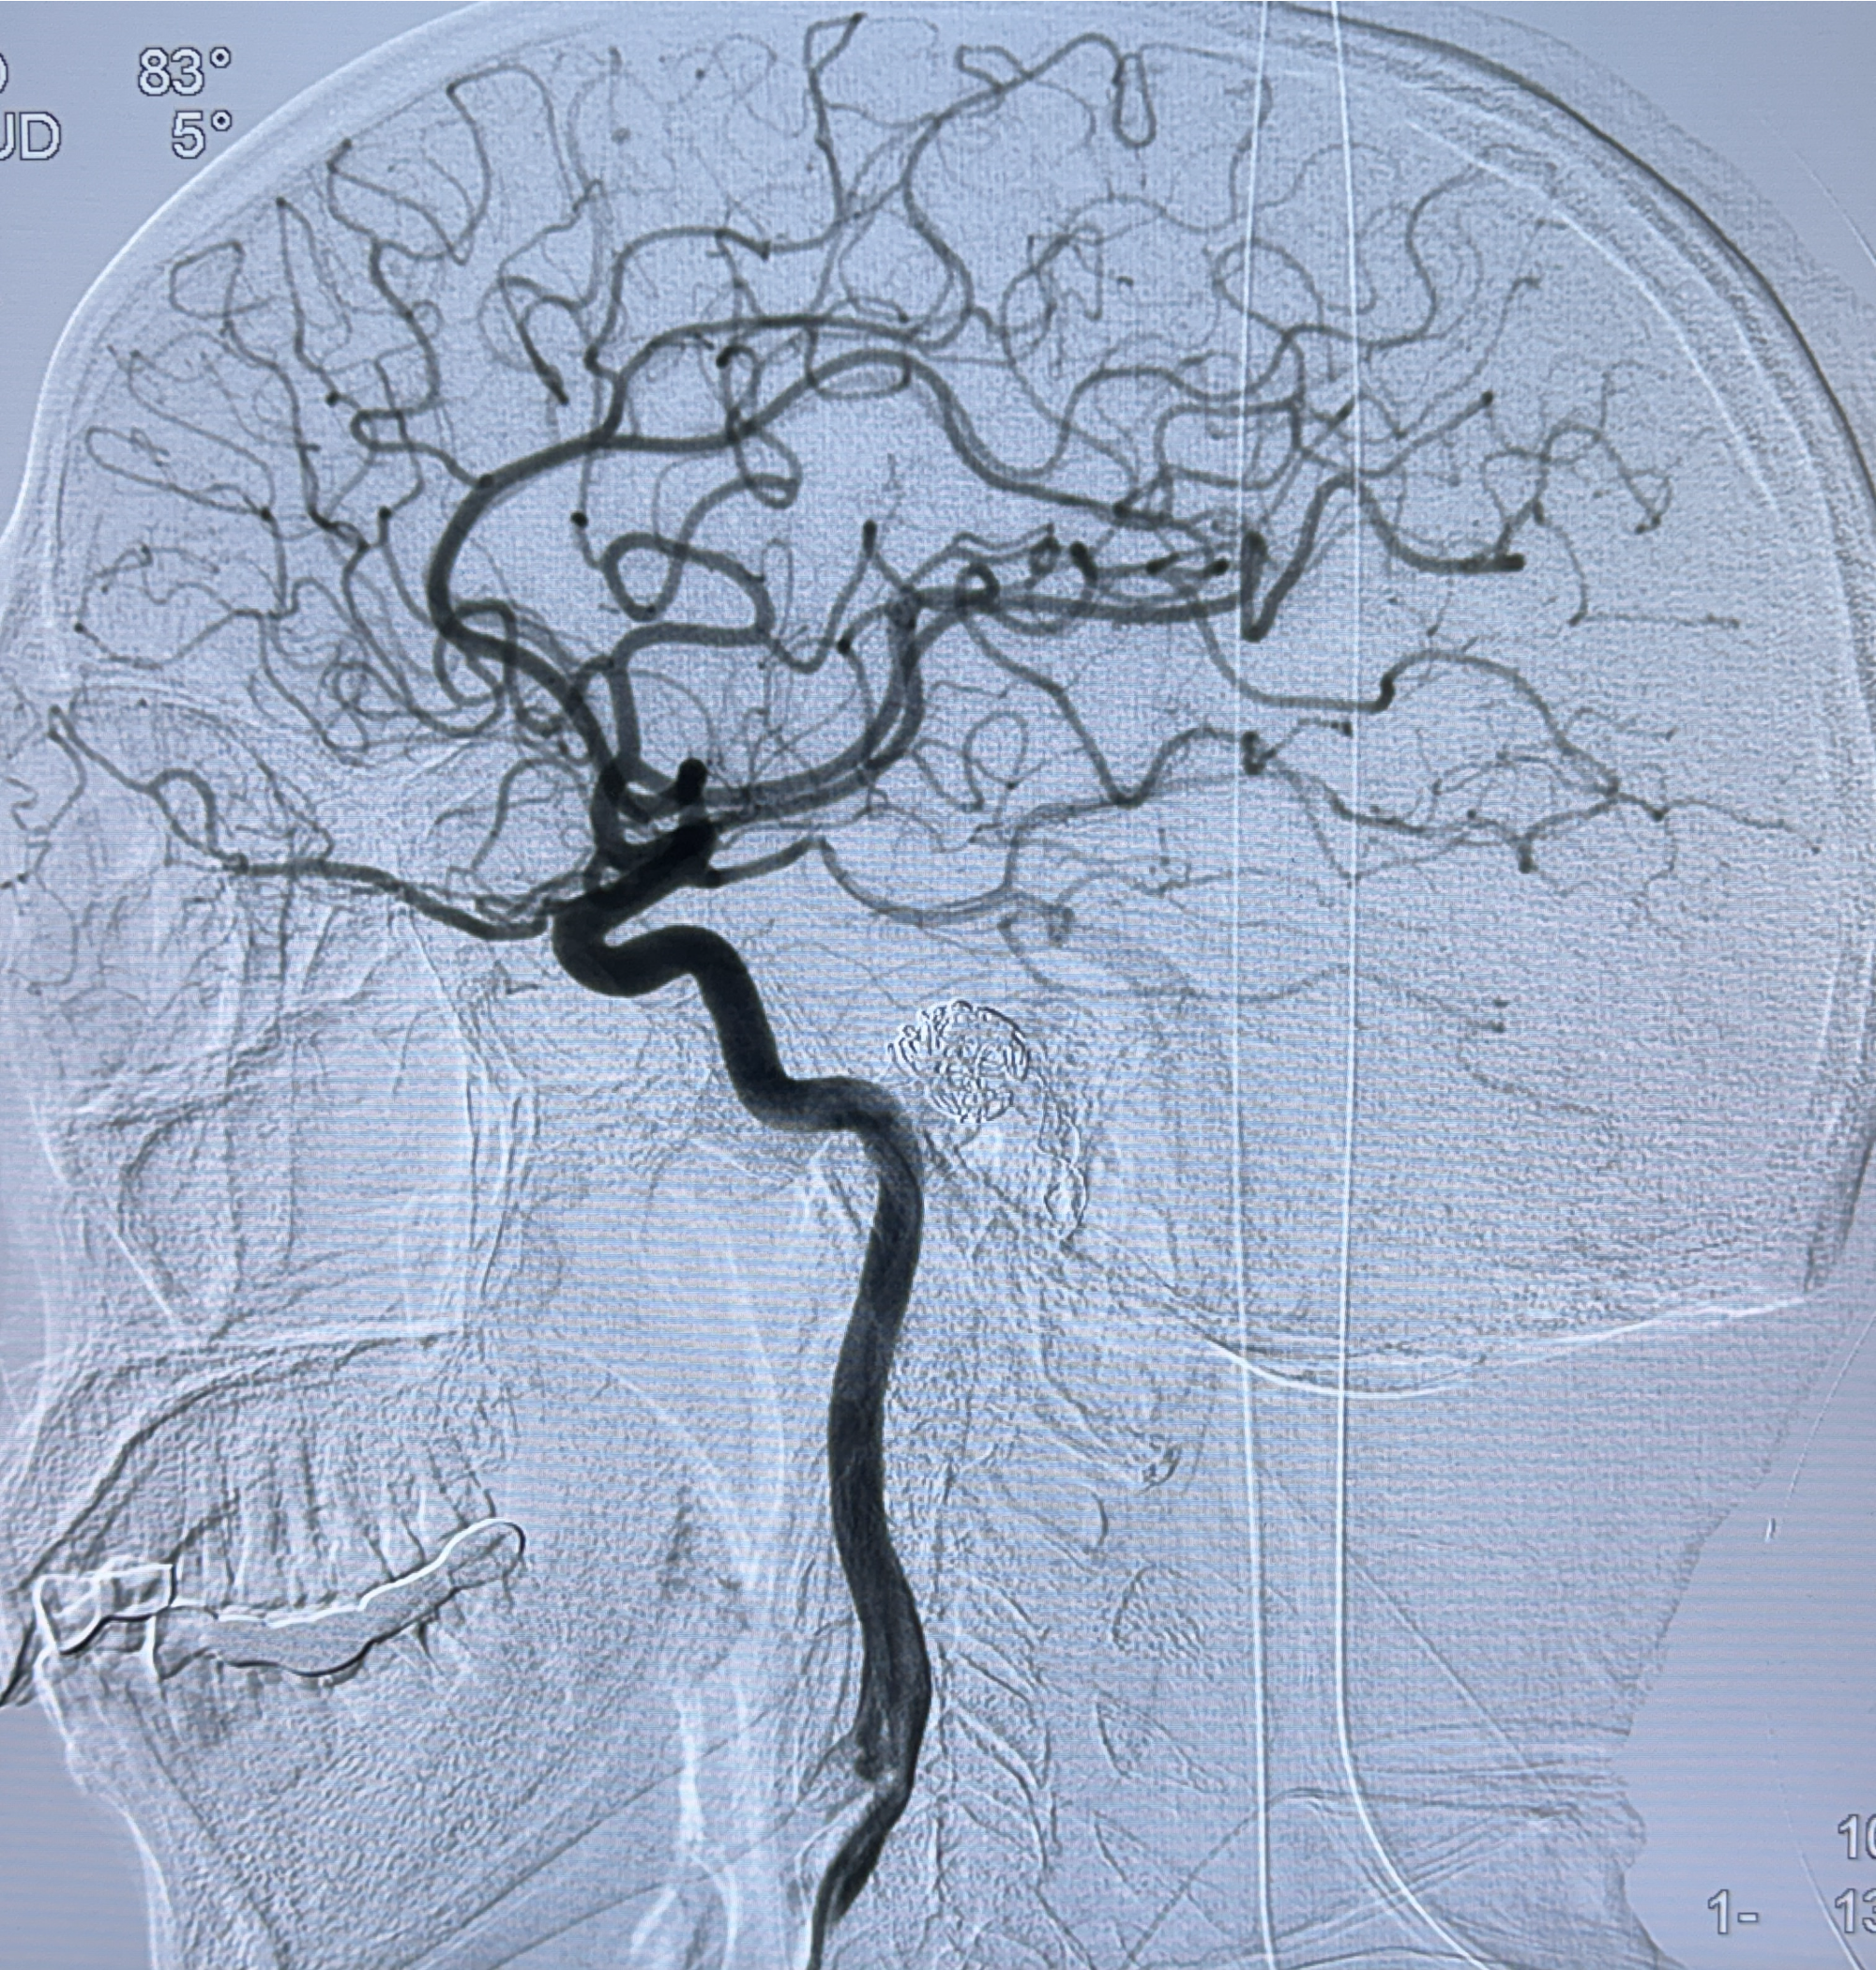

2024-01-08DSA:右侧椎动脉V4段夹层动脉瘤双支架辅助弹簧圈栓塞术后

患者支架辅助治疗后18个月,动脉瘤痊愈